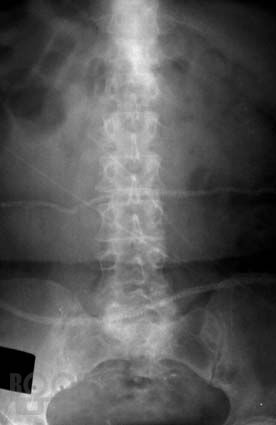

Практическое руководство «Рентгенодиагностика позвоночника для мануальных терапевтов» обобщает многолетний опыт сотрудничества автора – рентгенолога с мануальными терапевтами и освещает проблемы лучевой диагностики с точки зрения мануальной терапии. В руководстве представлен метод системного анализа рентгенограмм позвоночника. Особое внимание уделено клиническим аспектам применения данного метода в практике мануальной терапии: отражены методики экспресс-диагностики пространственного положения структур краниовертебральной зоны, позвоночника и крестца, описаны способы распознания, регистрации, хранения и передачи данных об индивидуальных характеристиках позвоночника каждого больного. Приведены классификации, рентгенологические проявления и особенности диагностики аномалий развития позвоночника в практике мануальной терапии. Показаны возможности и перспективы метода системного анализа рентгенограмм позвоночника для совершенствования лучевой диагностики в мануальной терапии и в восстановительной медицине. Руководство содержит большое количество рентгенограмм, схем, рисунков и таблиц.